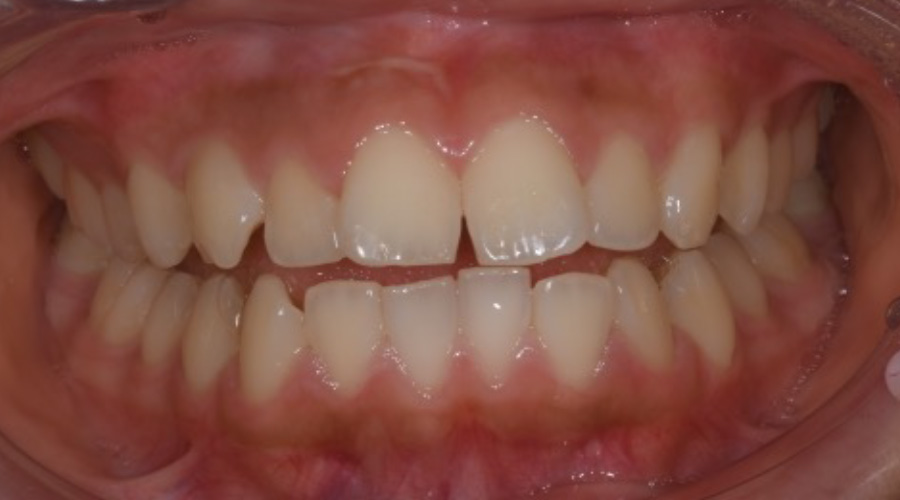

右上右下の八重歯、

下の歯のガタつき、

上の前歯の突出感が気になる

【マウスピース矯正】

- 主訴

- 右上右下の八重歯、下の歯のガタつき、上の前歯の突出感

- 期間

- 2年

- 費用

- マウスピース矯正

1,024,000円(税込)

- 治療内容

- 目立ちにくいマウスピース矯正(非抜歯矯正)

歯と歯の間に隙間をつくることにより、歯列弓を広げながら治療を行いました。

- 治療に伴うリスク

- ・後戻りする可能性があるのでリテーナーを最低でも矯正期間以上はつけること

・稀にほっぺた、唇、舌などに口内炎や傷ができることがあります